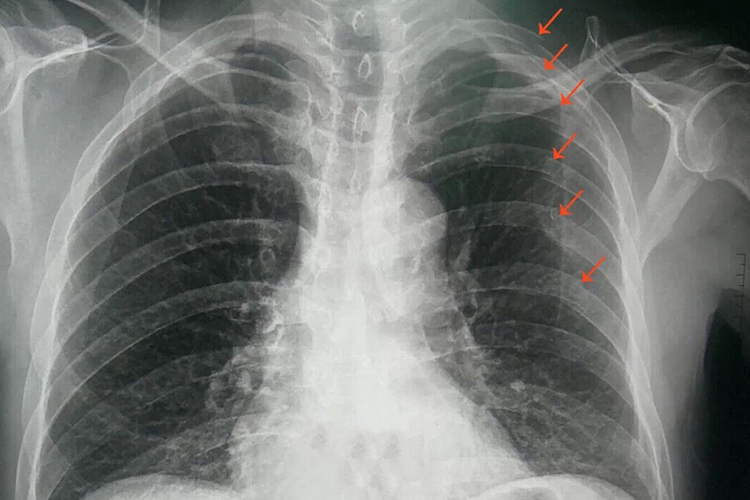

2、骨折的数量:有多根肋骨发生轻微骨折,疼痛可能会更加明显且持续时间更长,多根肋骨的骨折会增加胸廓的不稳定性,从而加重疼痛。